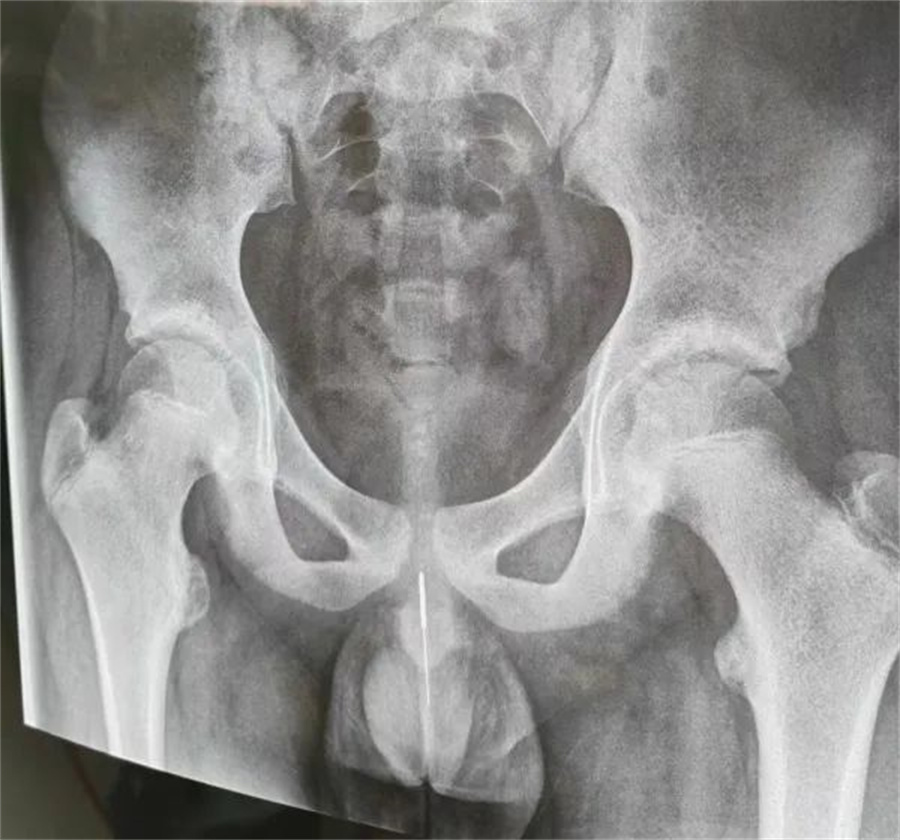

“孩子大概是中午的时候把银针塞进尿道中,因为针灸银针前段柔软纤细而末段又有增粗的螺旋状柄头,所以很难取出来。家长已经带他在当地医院拍片确诊,晚上7点多转到我们医院,当时孩子尿道口有血,疼痛难忍......”蜜桃视频

急诊外科接诊后立即收入院并第一时间做好手术准备,此时泌尿外科主任谢方达也紧急从家中赶到了医院,经过术前检查,确认银针卡在了接近球部尿道的部位,位置比较深,又没进入到膀胱里,如何尽快地取针成为一个颇具难度的挑战。

孩子家长和泌尿外科专家都希望用最微创的方式完成手术。但因孩子年龄小、尿道细,体重又偏大而难以实现,术中医生在保证对孩子造成伤害最小的前提下,采取隐匿小切口的方式,顺利将6.5cm的银针从尿道中刺破取出,为孩子解除了困扰,术后恢复三四天后即可顺利出院。